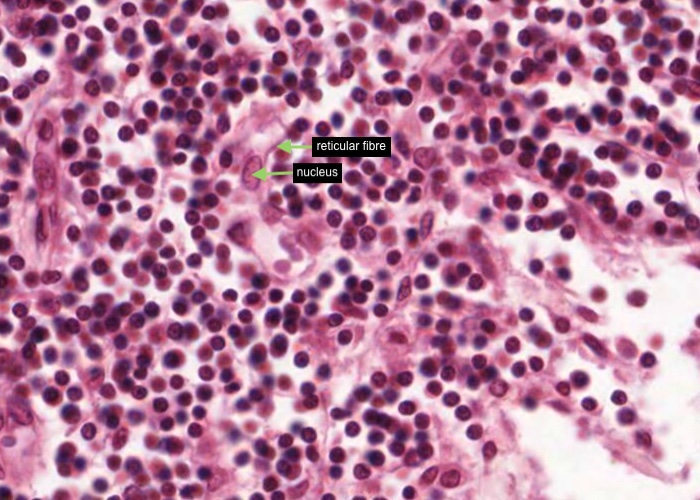

This section has been stained for reticular fibers. It shows the organization of the entire lymph node well, even though the cells barely show up.

At appropriate magnification (view the section via the link below) you will be able locate, the capsule, with its underlying sinus, trabeculum, medullary cords, vessels in the hilum, lymph nodules, and even their germinal centres. All of these structures are mapped out in reticular fibres. In fact, it is the stroma - the reticular cells stretched out along these fibers - that causes the various parts of the organ to form where they do.

Carefully examine the reticular fibres at high magnification. See that they form a supporting reticulum to house wandering cells.

When you examine the histological section find a place which shows that the reticular fibers are continuous with coarse Type I collagen fibres of the trabeculae and capsule. Type I collagen fibres stain brown instead of black because they have less carbohydrate on their surface.

Each reticular cell has an oval nucleus and cytoplasm stretched out along the reticular fibre.

Also at the bottom of this image there is probably some coarse Type I collagen fibres stained brown instead of black because they have less carbohydrate on their surface.

Again in this H&E section, each reticular cell has an oval nucleus and its cytoplasm is stretched out along the reticular fibre.